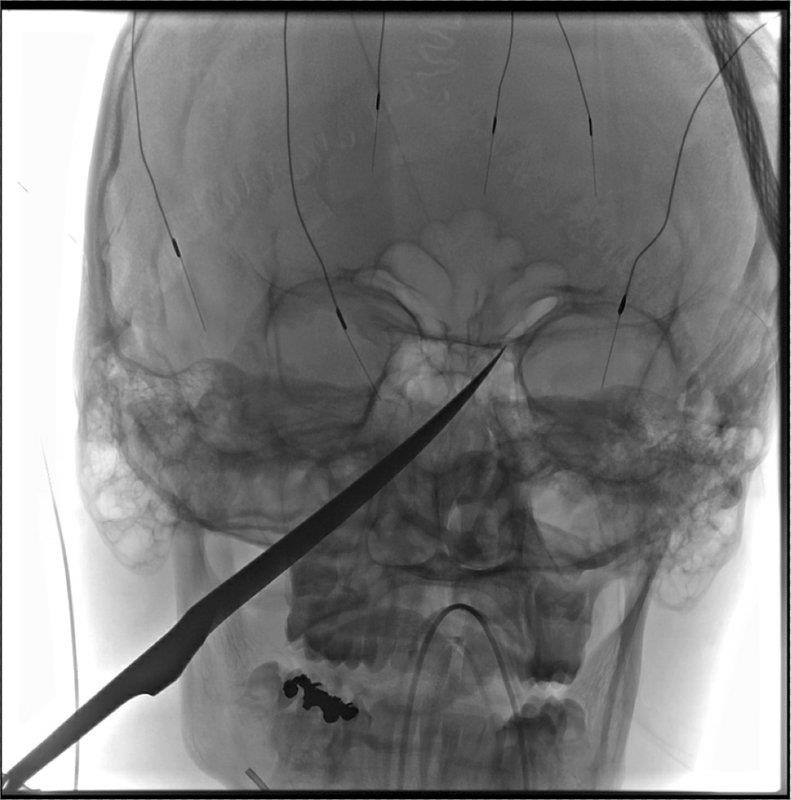

Lưỡi dao đã đâm xuyên vào hộp sọ và suýt chạm tới não của Gregg. Mũi dao khi đó gần chạm tới động mạch cảnh, nơi cung cấp máu cho não, theo AP.

| Hình chụp X-quang hộp sọ của Eli Gregg. Ảnh: AP. |